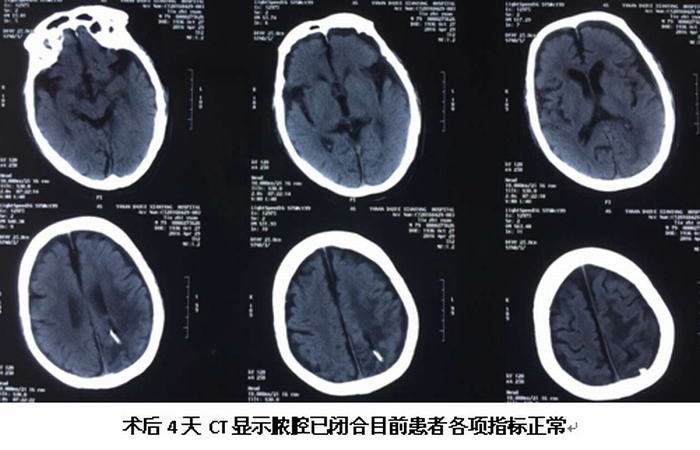

繼完成第一例腦立體定向手術(shù)后不久,于2016年4月25日我院神經(jīng)外科又完成一例89歲高齡腦膿腫患者的腦立體定向膿腫穿刺引流術(shù),按照手術(shù)標(biāo)準(zhǔn)流程操作,術(shù)中清除膿液約30ml,經(jīng)置管持續(xù)引流并局部及全身注射抗菌素治療,目前患者頭顱CT顯示膿腔已消失,體溫正常,神志清楚,各項生命體征平穩(wěn)。